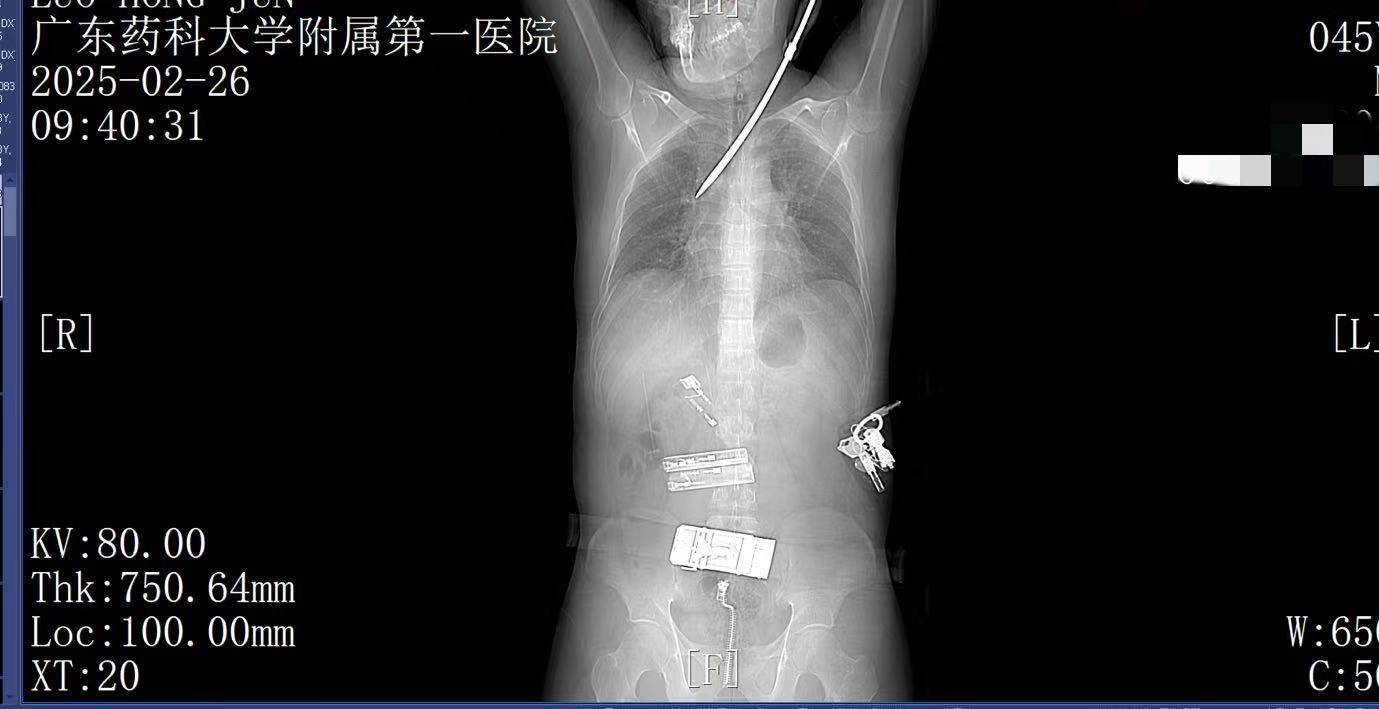

2月26日上午9时许,44岁的电梯工人罗师傅(化姓)正在广州某工地弯腰工作,突然一把螺丝刀从20多米高处坠落,刺中罗师傅的胸背部炒平台币。罗师傅当即疼痛难忍,呼吸困难。工友立即呼叫120。一场惊心动魄的生死救援立即展开。

9:22,广东药科大学附属第一医院救护车到达现场,查看患者伤情后,黄业君主治医师立即固定好螺丝刀,避免再次移动损伤神经血管,并马上电话联系医院后方,医院急诊科主任曾育辉立即通知心胸外科、脊柱外科等相关科室紧急会诊炒平台币。

9:39,救护车到达医院大门,院内急救团队已经做好准备炒平台币。在紧密监护的情况下,全程采用绿色通道。到达医院时,罗师傅已经面色苍白,呼吸急促。螺丝刀已深深刺入罗师傅右肺,随时可能因大出血而危及生命。

9:41,快速完成头+胸+腹部CT检查,经多学科会诊,明确螺丝刀异物刺入肺部炒平台币。CT显示螺丝刀紧贴肋间血管、上肺后段动脉,尖端距右肺门仅2厘米,一旦贸然拔出螺丝刀,极有可能引发大出血,导致失血性休克甚至死亡,必须紧急手术。